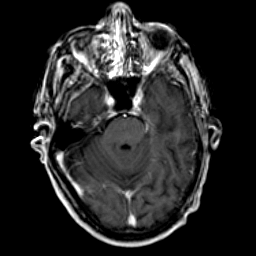

Glioma Overlay -- Slice #6

[Home][Help][Clinical] Slice 6